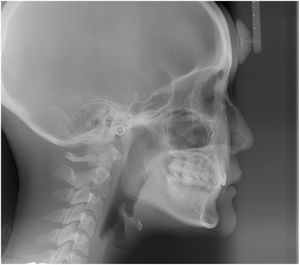

治療前 の 横顔レントゲン です 動く矢印治療後 の 横顔レントゲン です